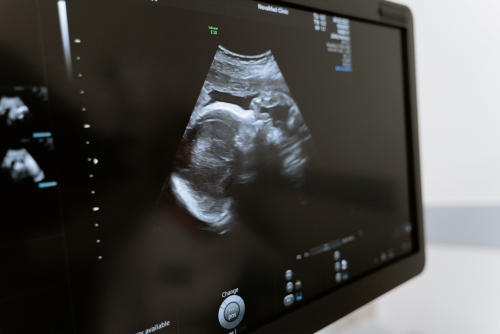

小排畸是常規超聲檢查嗎?—平創醫療

常規超聲檢查指的是二維超聲檢查,二維超聲檢查即二維超聲檢查,小排畸是為了更好地觀察胎兒生長發育情況,排除畸形的檢查。小排畸檢查能夠排除絕大多數胎兒畸形,如先天性心臟病、唇腭裂、水腫胎,以及多指畸形、重度腦膨出等。

1、先天性心臟病:可通過二維超聲檢查直接觀察心臟及大血管的形態、結構、連續性及血流改變,二維超聲檢查比較直觀,能夠顯示出心臟的三維圖像,所以在懷孕期間需要定期做產檢,一般在懷孕20-26周需要做四維彩超大排畸檢查,判斷胎兒是否有畸形;

2、唇腭裂:二維超聲檢查能夠比較清晰地顯示出胎兒嘴唇及面部發育情況,而且還能夠觀察到是否存在唇腭裂的情況,所以在懷孕期間需要常規做三維彩超檢查,判斷胎兒是否存在唇腭裂;

超聲檢測2

3、水腫胎:如果孕婦出現水腫胎,也需要做二維超聲檢查,判斷胎兒是否存在水腫胎,因為如果孕婦出現水腫胎,大多是由于妊娠期高血壓導致,所以在懷孕期間要定期做產檢,隨時觀察水腫胎的情況;

4、多指畸形:產前二維超聲檢查可以觀察到胎兒手指、腳趾等外觀畸形,如果出現多指畸形,還需要做三維超聲檢查,判斷是否有多指畸形的情況;

5、重度腦膨出:二維超聲檢查能夠比較清晰地觀察胎兒腦組織、脊柱、羊水等情況,如果出現重度腦膨出,也需要做三維超聲檢查判斷是否有腦積水。

孕期需要做好定期產檢,建議在懷孕24-26周需要到醫院做四維彩超大排畸檢查,判斷胎兒是否有畸形,如果出現比較嚴重的畸形,建議在醫生指導下終止妊娠。